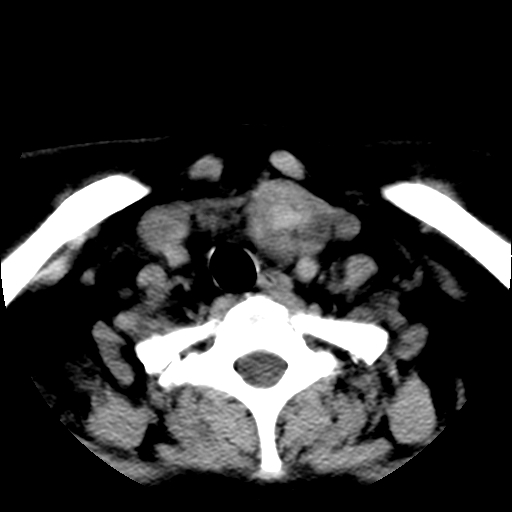

标题: CT25491:女,55岁,发现左侧甲状腺肿块一个月。 [打印本页]

女,55岁,发现左侧甲状腺肿块一个月,彩超示:甲状腺多发结节伴左叶结节液化。

多考虑甲状腺腺瘤。

考虑甲状腺腺瘤。

腺瘤囊变